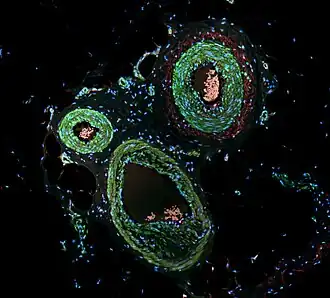

Immunofluorescence is employed in foundational scientific investigations and clinical diagnostic endeavors, showcasing its multifaceted utility across diverse substrates, including tissue sections, cultured cell lines, or individual cells. Its usage includes analysis of the distribution of proteins, glycans, small biological and non-biological molecules, and visualization of structures such as intermediate-sized filaments.[8]

Examination of immunofluorescence specimens can be conducted utilizing various microscope configurations, including the epifluorescence microscope, confocal microscope, and widefield microscope.[12]